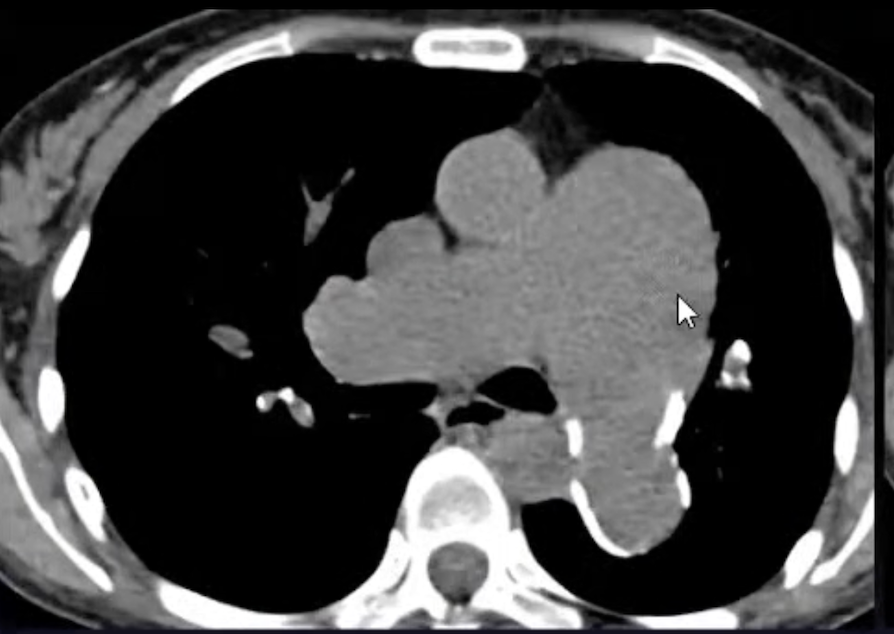

A

Hipertensão arterial pulmonar

Sinais radiológicos da HAP

• Dilatação de artéria pulmonar central

• Estreitamento abrupto ou afilamento de vasos pulmonares

• Aumento de VD e AD

• Dilatação de artérias brônquicas

• Atenuação em mosaico (perfusão pulmonar)

- esquistossomose

Hipertensão pulmonar

Relação artéria-brônquio

Sinais de hipertensão arterial pulmonar

Hipertensão arterial pulmonar em esclerodermia